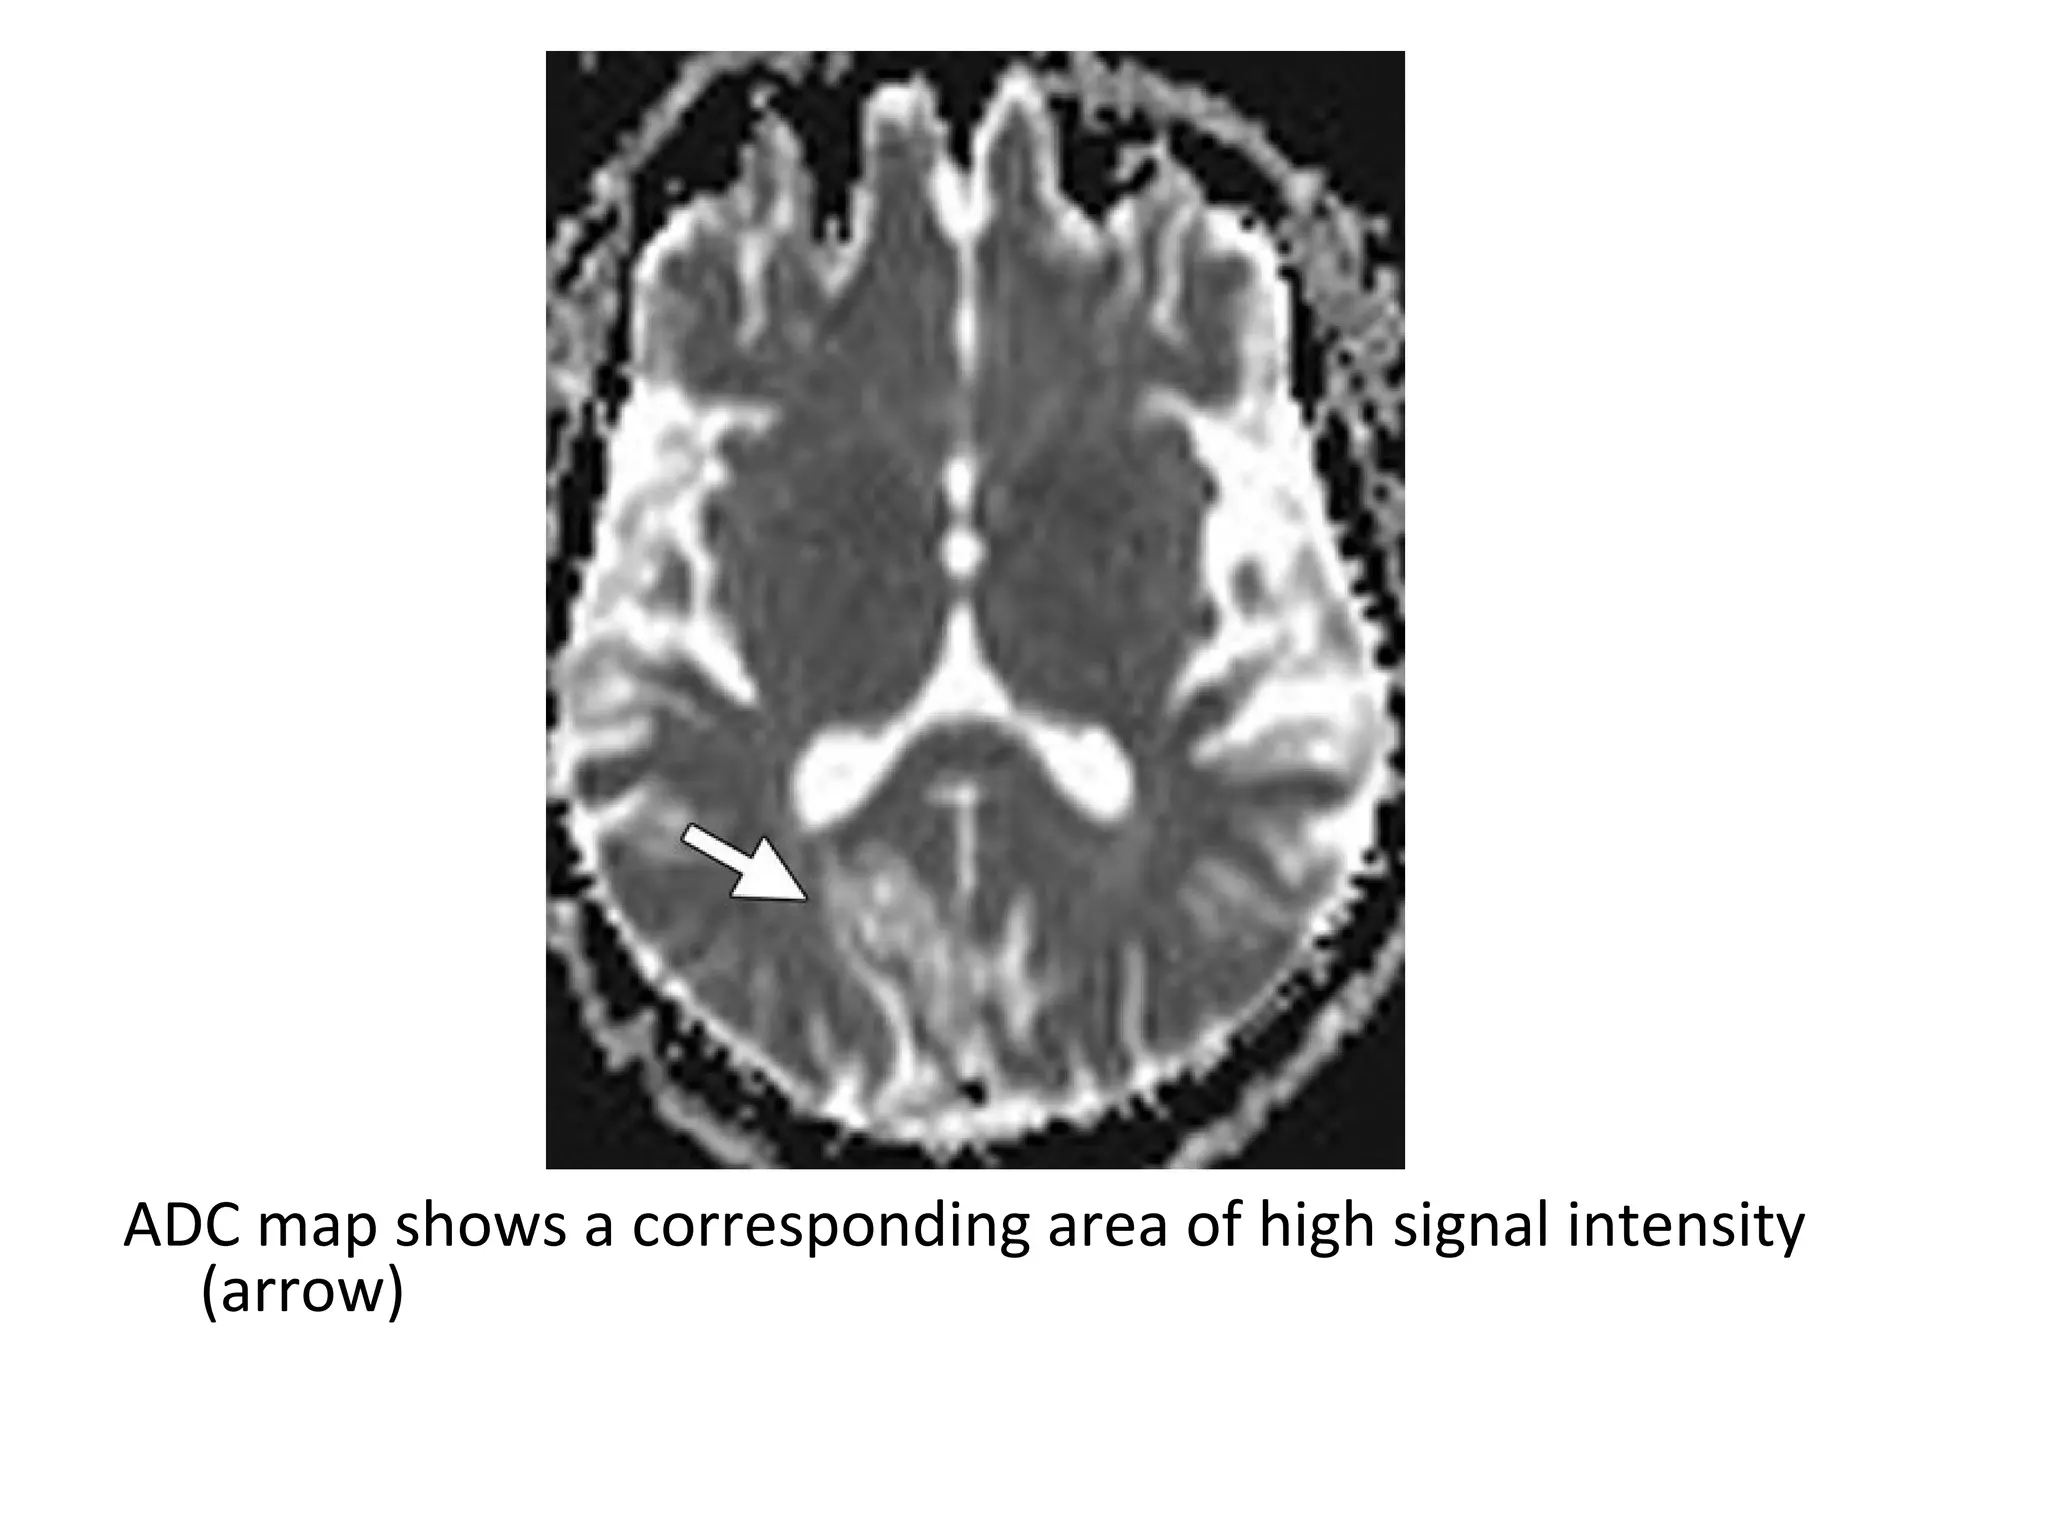

DWI shows an area of low signal intensity in the right occipital lobe (arrow)

with a peripheral rim of high signal intensity , a finding that may be due to

T2 shine-through

ADC map shows a corresponding area of high signal intensity

(arrow)